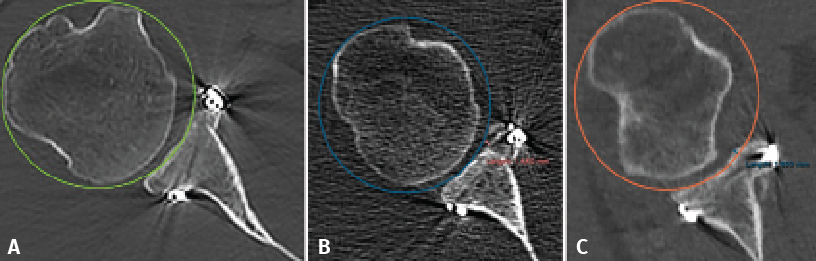

Figure 1. Estimation of glenoid axis and height according to the method of Barth(13). Two circumferences are traced: one lower, taking the posteroinferior glenoid border as reference, and one higher than the other and tangential to the glenoid borders. The line joining the centre of both circumferences is taken to represent the axis of the glenoid cavity. Over this, the height corresponding to half of the glenoid cavity and to 25% is established.

Taking the posteroinferior glenoid border as reference, we traced a first circumference over its contour, and a second circumference above the previous one and tangential to the glenoid borders. The line joining the centre of both circumferences was taken to represent the axis of the glenoid cavity. Over this we estimated the point corresponding to the half and 25% of the glenoid height (Figure 1). The sagittal section was used to determine the position of the graft in the craniocaudal direction (Figure 2). The length (in mm) of the bone defect was measured (B), along with the amount of bone graft covering the defect (A). Percentage covering of the bone defect was estimated from the ratio between A and B. The graft was considered to be well positioned when the percentage coverage of the defect was at least 90%.